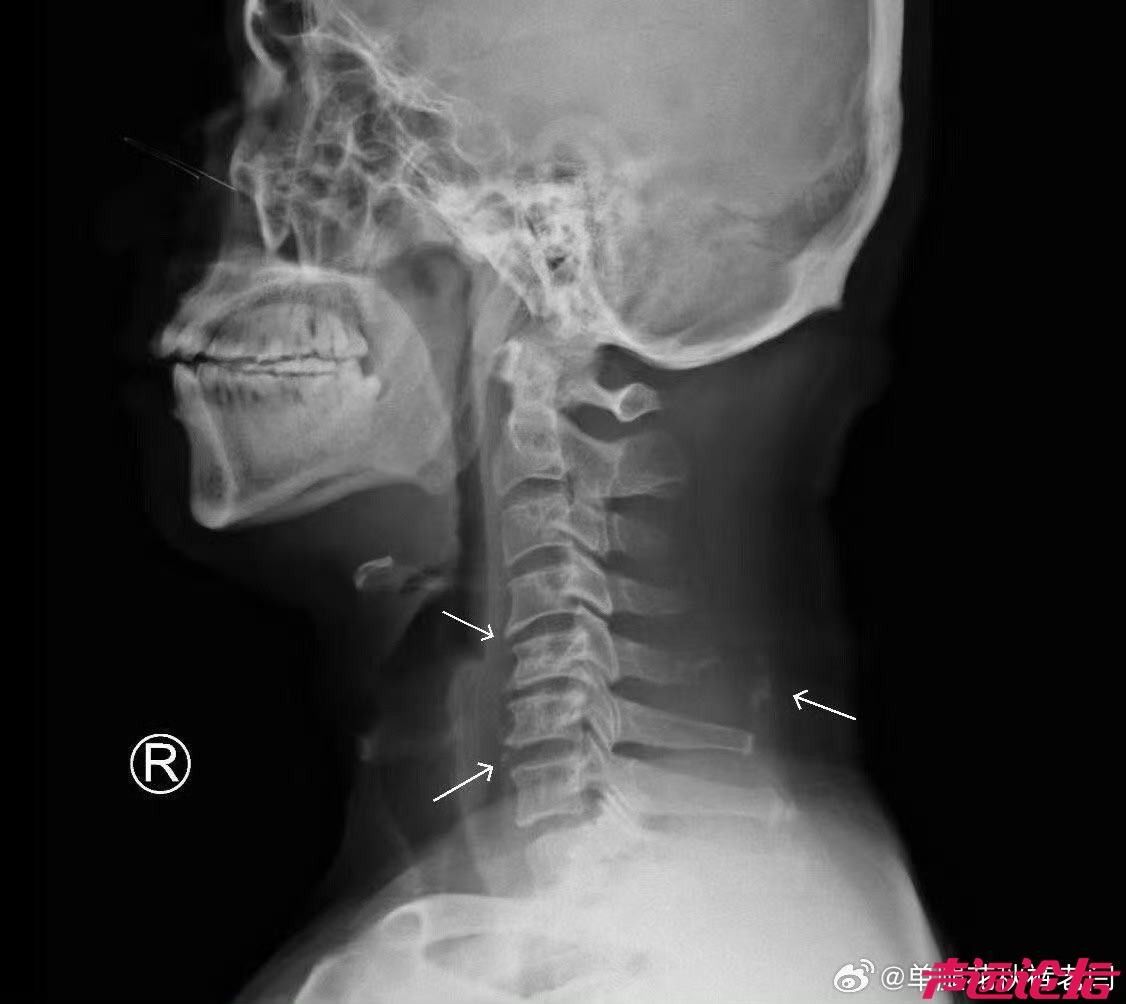

颈椎病不一定都是脖子疼

脑梗塞、眩晕、肩周炎、甲状腺疾病、哮喘、咽喉问题及咳嗽,手指、手臂麻木酸疼,心血管病等颈椎问题值得大家关注